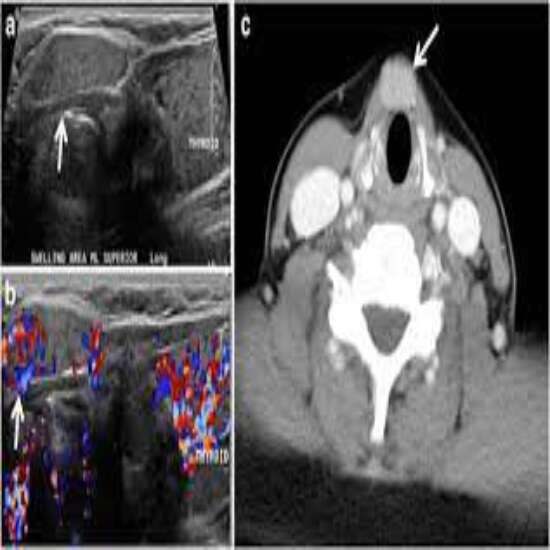

Thyroid color doppler is a type of ultrasound imaging technique that is commonly used for screening, diagnosing and monitoring patients with Thyroid disorders. It evaluates the soft tissues of thyroid gland and provide real time speed, direction and pattern of blood flow in thyroid vessels

Color doppler imaging of thyroid gland is a fast technique for the evaluation and assessment of Thyroid disorders which are very common in females. Also, it offers high sensitivity and specificity in differentiating benign thyroid nodules from malignant ones.